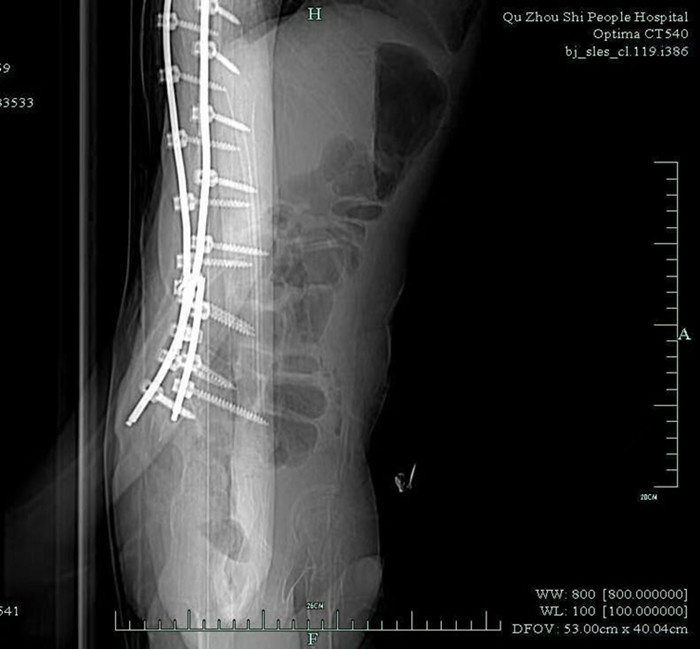

早就收過(guò)病危通知書(shū)的小徐,由于沒(méi)有肌肉力量的支撐,大部分骨骼被擠壓變形。體重不足40公斤的他,幾年前因?yàn)榧怪鶄?cè)彎,靠著打進(jìn)身體里的37枚鋼釘,才勉強(qiáng)能在輪椅上坐穩(wěn)。

鞘內(nèi)注射是神經(jīng)內(nèi)科醫(yī)生的基本操作,本身并沒(méi)有多大難度。但由于小徐長(zhǎng)年疾病導(dǎo)致脊椎側(cè)彎,椎管變得彎彎曲曲,還有37根鋼釘橫亙其中,這讓原本并不復(fù)雜的注射治療變得十分困難。